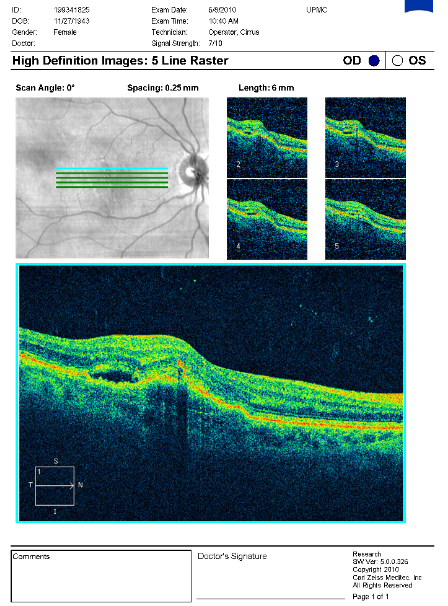

FUNDUS DESCRIPTION: |

OD OS |

OD Red-Free: Pre-Injection: Arterial: A-V: Venous: Recirculation: Late:

OS Red-Free: Venous: Recirc: Late:

Impression